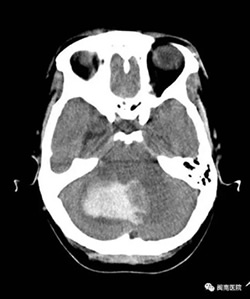

2017年3月19日凌晨,一位50多岁的王阿姨突发眩晕,意识障碍,送到我院闽南医院,急查CT确诊为小脑出血,血量达30ml,血压高达210/120mmHg,如不尽快做手术,病人将危在 旦夕!然而,据家属描述,病人还有脑梗塞病史,手术的话病人则很可能在手术台上发生危险!

众所周知,心脑血管疾病是威胁人类健康的头号杀手,而出血性中风是其中的一大类型疾病,它往往在情绪激动及使劲用力后诱发,因其“高死亡率和高致残率”给家庭和社 会带来沉重的负担。对待这种急重病人,在区县级医院里的一般大夫,要么选择非手术的保守治疗,要么建议转院处理,且病人家属也往往要求转院。万幸的是,当天外科值班的 医生正是我院本部神经外科副主任医师江常震大夫,作为福建省内神经外科界知名的医生,江大夫马上做出了急诊手术的决定,并告知家属急诊手术的迫切性和必要性。家属商讨 后决定留在闽南医院抢救。艺高人胆大,神经外科医疗组快速制定应对各类紧急情况的预案,随后在备血,降压及降颅压等充分的术前准备后,开始手术。

手术由江常震主刀,蔡明、杨旭耀、郭小洪医生作为助手配合手术。为防止颅压增高,脑疝形成,医疗组先给患者行“右侧脑室额角引流术”,为下一步小脑血肿清除、减压 赢得宝贵的时间。为了使患者头部在手术中保持稳定以利小脑的显露及减少小脑创伤,医疗组利用“三点”式头架固定头位,全程利用精巧的显微器械沿着颅内自然间隙进行操作 。

脑出血手术清除血肿过程中最关键的步骤是止血,此时高位波动的血压、动脉粥样硬化的血管和血肿周围水肿的脑组织给止血带来了极大的挑战,但是江大夫沉着冷静、从容 不迫,经过5个多小时的手术,病人的血肿全部清除,出血点也得到了有效控制。为做好术后围手术期管理,术后江大夫带领神经外科团队每天蹲守在重症监护室(ICU)密切观察 患者病情变化,指导管床医师处理及用药,确保病人平安度过危险期。而且,在回到普通病房后,江大夫还积指导病人做康复功能锻炼。历时近一个月,在医生的协助下,病人终 于战胜了病魔,痊愈出院。病人及家属对治疗效果非常满意,并为江大夫的精湛技术点赞。因江常震大夫是神经外科专家,大家私底下亲切地称他为“江神医”。